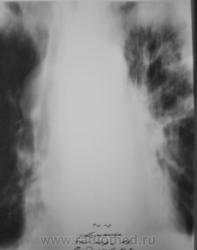

В последнее время пациент затежелел и был госпитализирован в областное ЛПУ, где было проведено несколько исследований.

1. Исследовавние.

2 Исследование.

В связи с появившейся осиплостью голоса пациенту была проведена томография гортани.

3. Исследование.

На следующий день после томографии гортани была произведена томография верхушек.

4. Исследование.

Пациент был выписан под наблюдение онколога по месту жительства.